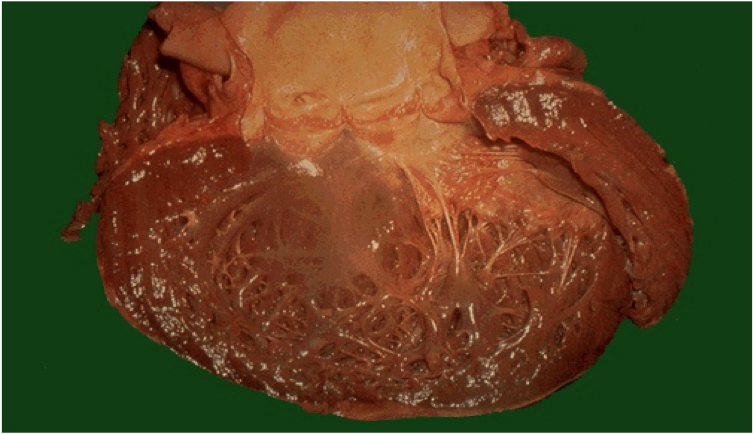

Which type of heart valve is seen here?

atrioventricular valves

note the chordae tendinae connecting to the papillary muscles

also called leaflets